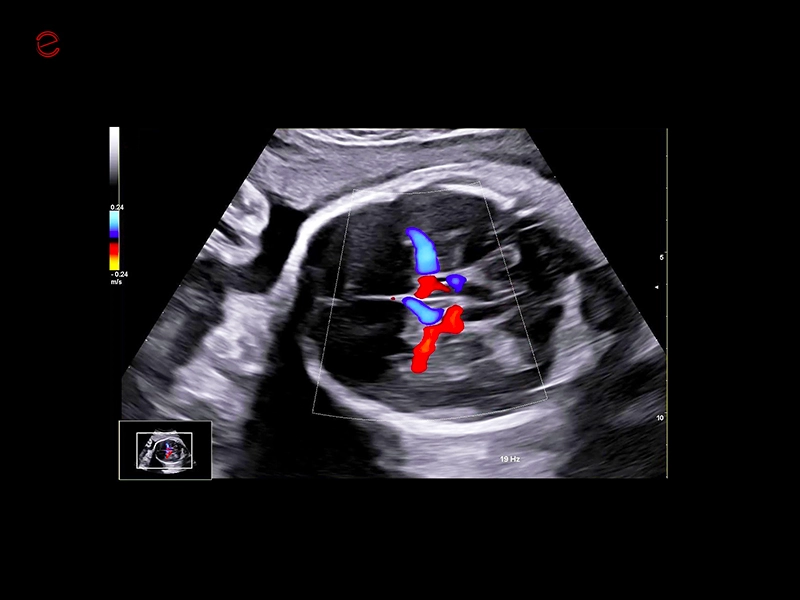

MyLab™9 Platform - Ultra-sensitivity Colour Doppler for precise visualization pulmonary veins

MyLab™9 Platform - Ultra-sensitivity Colour Doppler for precise visualization pulmonary veins